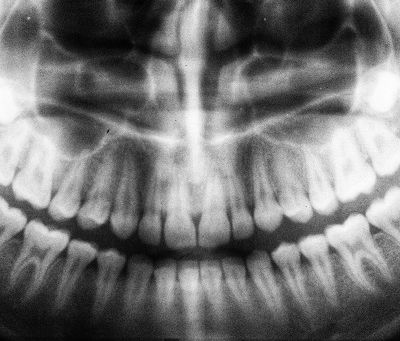

Why Panoramic X-Ray Is Essential Before Braces

When starting orthodontic treatment, accuracy and planning are the keys to success. One of the first steps most orthodontists take is to...

Dental Panoramic X-Ray: What It Reveals About Your Teeth

When it comes to modern dentistry, diagnostic precision is the foundation of effective treatment. One of the most advanced tools for...

Dental Panoramic X-Ray Benefits for Oral Surgery

When it comes to oral health, early and accurate diagnosis is key to preventing complications and ensuring the best possible treatment...

What Is a Dental Panoramic X-Ray?

Dental imaging has become an essential tool in modern dentistry, providing detailed insights into oral health that a visual examination...